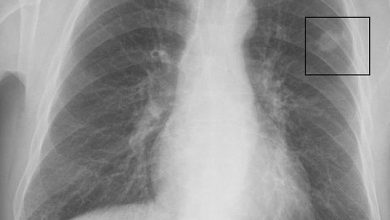

أسباب سرطان الرئة و أنواعه و أعراضه

يعتبر السرطان نمو غير طبيعى للخلايا يسبب تدمير أنسجة سليمة فى الجسم و منها ينتشر لباقى أنحاء الجسم، و يعتبر…